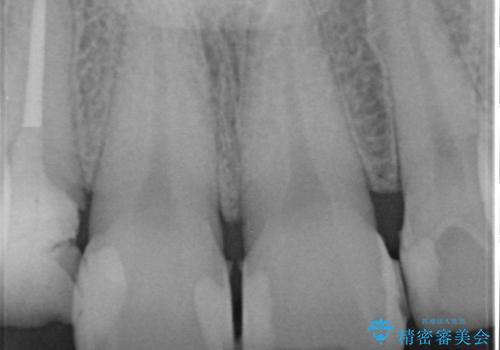

- 前歯の虫歯に気付きながらも放置し、一念発起し治療を希望され来院されました。

虫歯のマイクロスコープによる丁寧な除去、根管治療、深い虫歯に対する挺出(エクストリュージョン)および歯周外科を行ったのち精度の高いセラミッククラウン製作治療を計画します。

虫歯の放置により、根管治療や深い虫歯に対する処置が必要になりましたが丁寧に一つづつ処置を行ったことで抜歯をすることなく歯を残すことができました。

セラミッククラウンの製作をする前に、歯内・歯周環境の整備は非常に大切です。